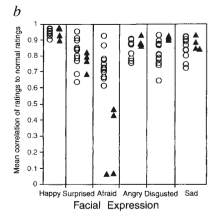

Patients with amygdala damage exhibit diminished emotional fear recognition and expression

Patient S.M. can’t recognize the emotion of fear in photographs. She also exhibits little fear herself (e.g. to dangerous animals, scary houses, films, etc)

Note:

patient SM has rare autosomal recessive condition called Urbach-Wiethe disease. Disorder of bilateral calcification an atrophy of anterior-medial temporal lobes. Both amygdalas are extensively damaged. Little to no injury of the hippocampus.

She has no motor or sensory or intelligence or memory or language impairment. However she can’t recognize the emotion of fear in photographs. Furthermore, she exhibits little fear herself (to dangerous animals, scary houses, films, etc).

Patients with amygdala damage exhibit diminished emotional fear recognition and expression

Note:

Adolphs et al., 1995. Subject with bilateral amygdala lesions was asked to draw facial expressions of emotions.